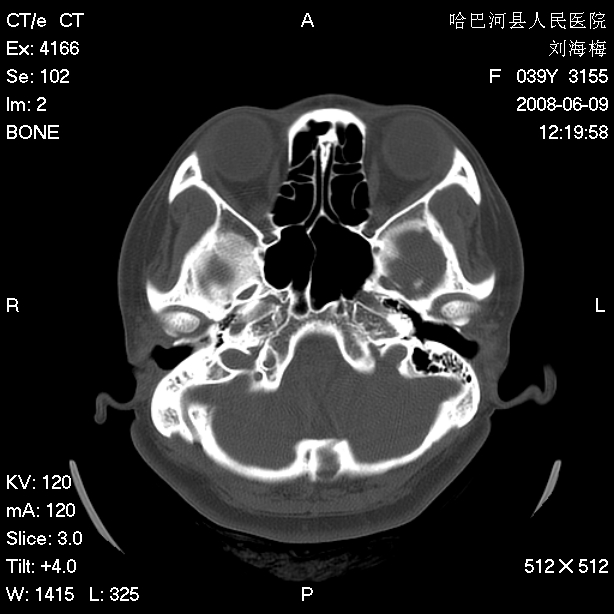

标题: CT13909:F39Y,头痛1年 [打印本页]

标题: CT13909:F39Y,头痛1年

头痛1年

枕骨蛛网膜颗粒压迹。

嗜酸性肉芽肿?骨髓瘤?不像蛛网膜颗粒压迹,太大了,并且有占位效应。

枕骨胆脂瘤

1.应该考虑表皮样囊肿

2.右中耳乳突应薄扫!

支持蛛网膜颗粒压迹,右中耳乳突应薄扫!

支持枕骨胆脂瘤可能性最大。右侧乳突部密度增高,建议薄扫。